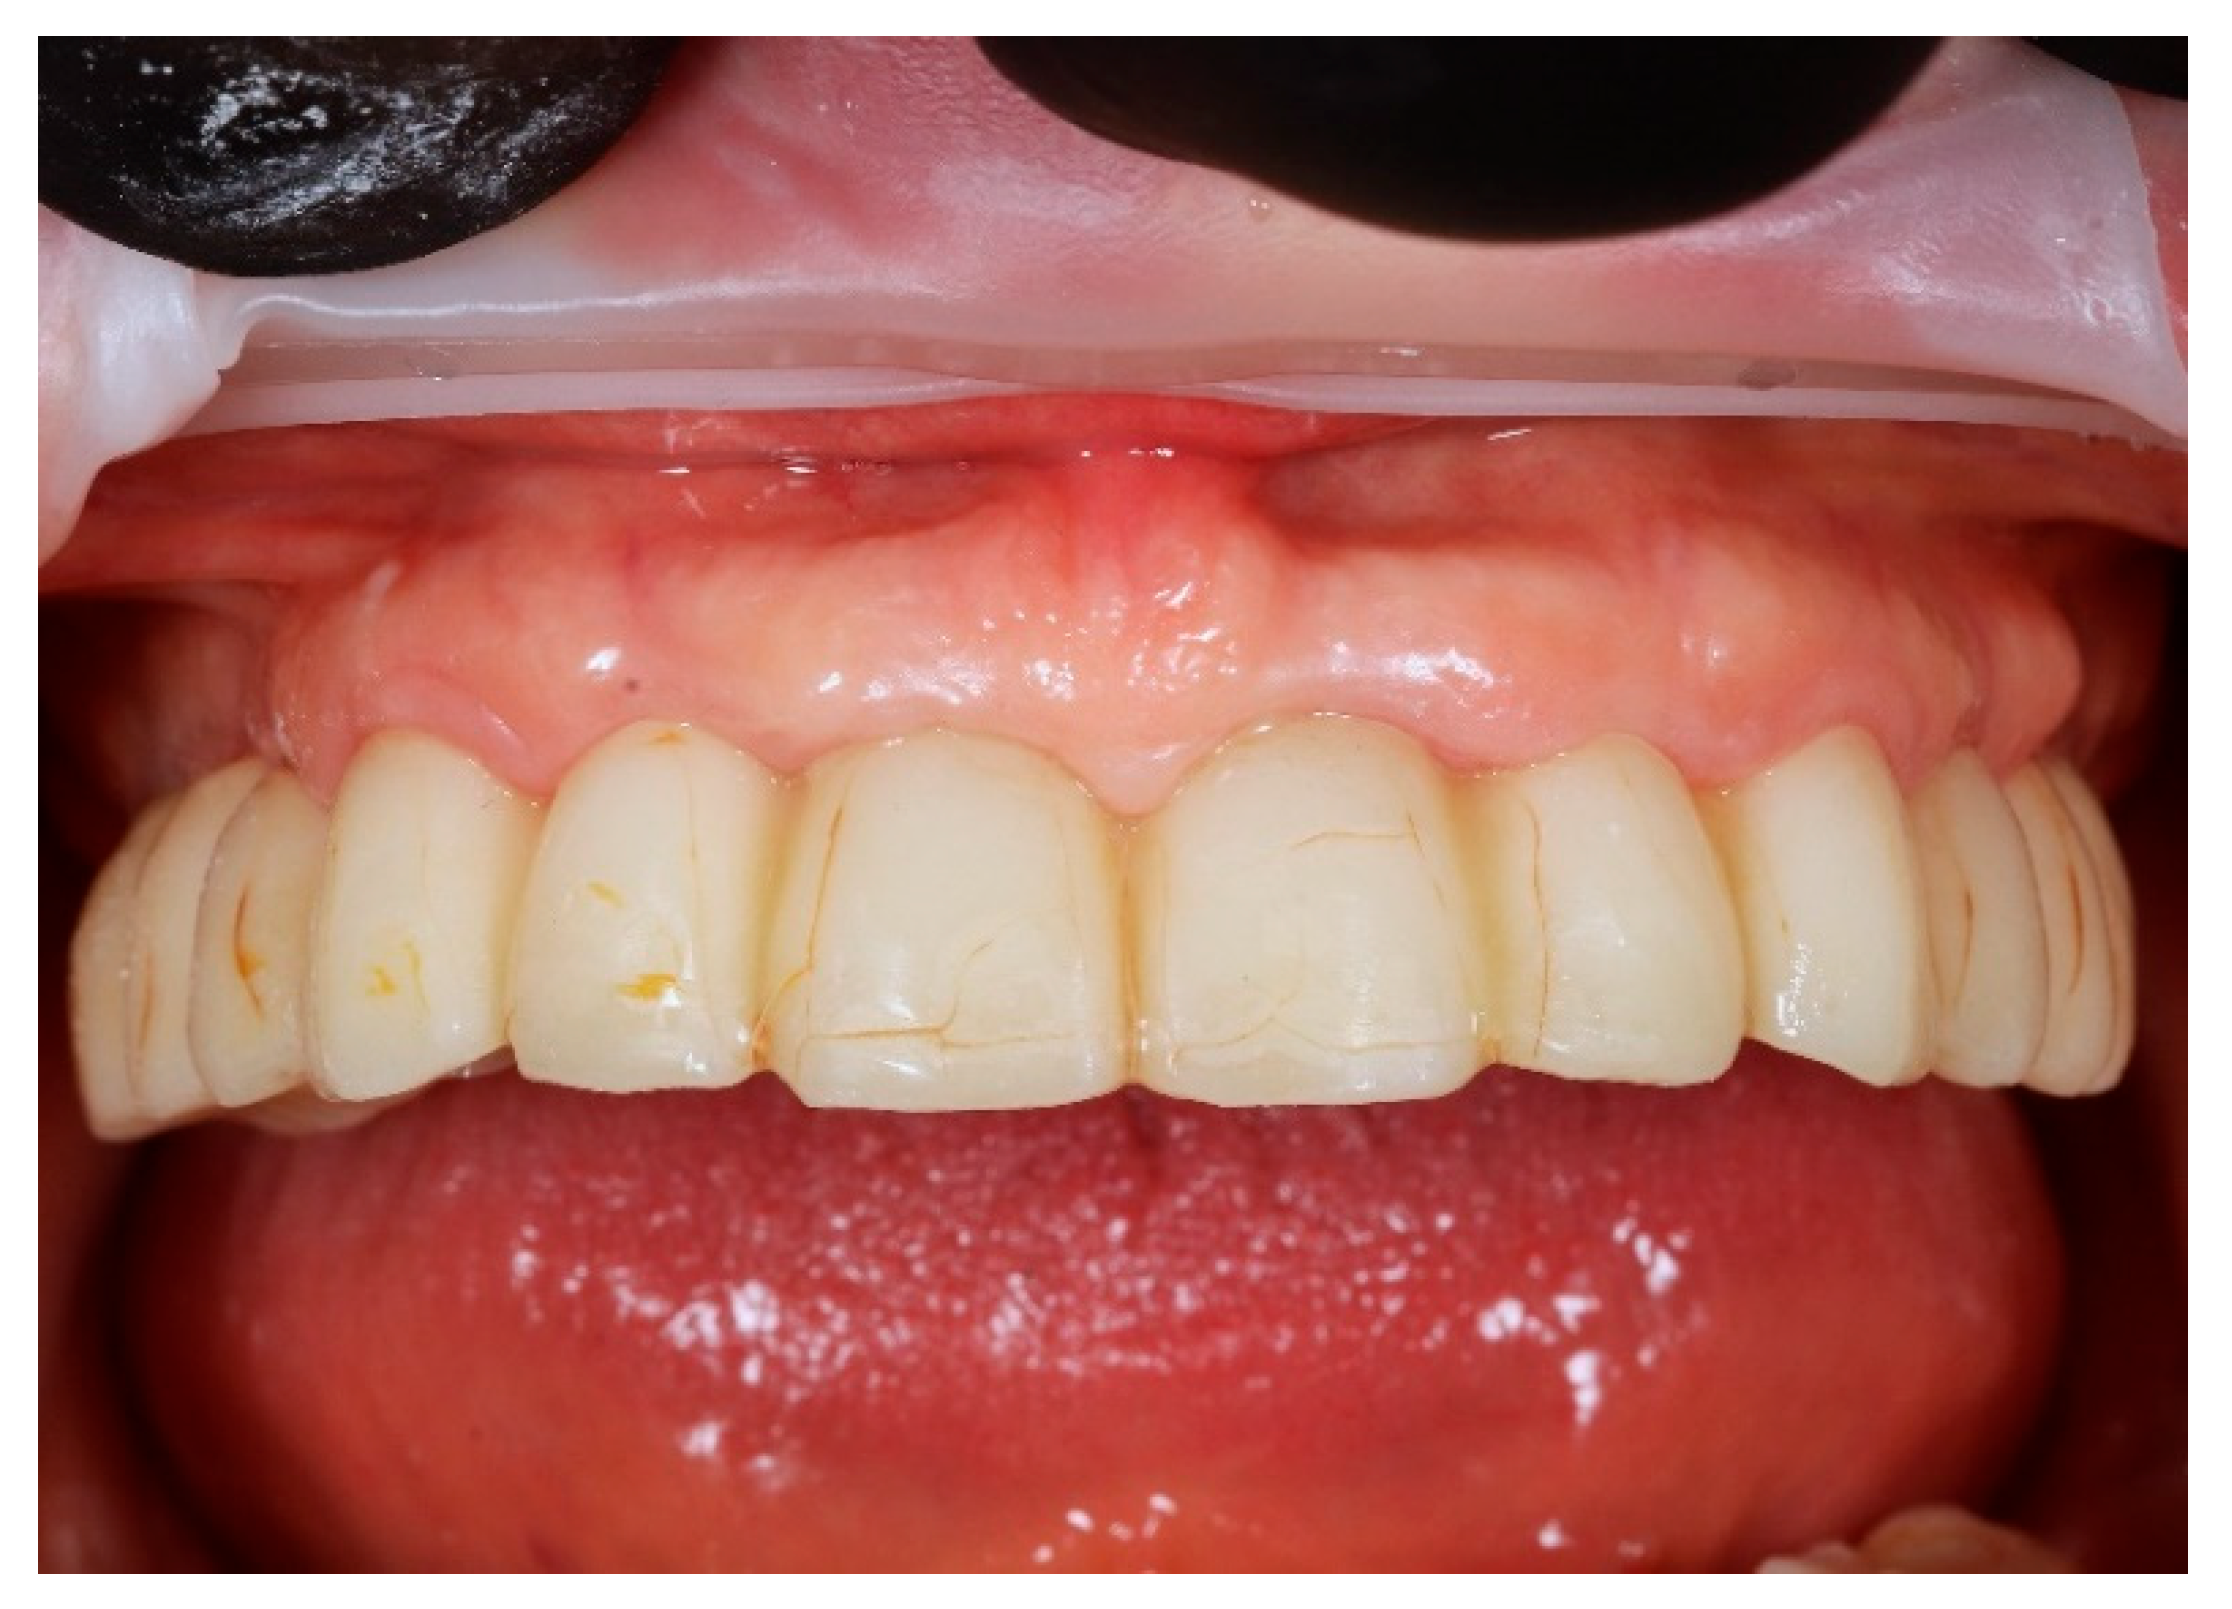

Finally, the prosthesis was delivered by fixing to the multi-unit abutments with screws. Clinical adjustments were performed to ensure perfect fit, occlusion, phonetics, and aesthetics. The patient reported immediate improvement in comfort and satisfaction compared to the acrylic splint (Figure 9 and Figure 10).

This early restoration provided stable occlusion, acceptable aesthetics, and proper phonetics while allowing progressive soft tissue conditioning. It also constituted the foundation for definitive prosthetic planning. The patient was instructed on hygiene maintenance and placed on a soft diet during the initial healing period.

Figure 10. Digitally planned, 3D-printed full-arch provisional restoration after the healing phase and fixed to the multi-unit abutments screws, shown in situ (front view).